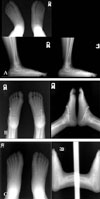

Bony union was defined as the evidence of obliteration of the osteotomy lines based on radiographic findings (Fig. 1). All patients followed radiological evaluation with standard anteroposterior and lateral views of the foot in standing position.8 The talo-1st metatarsal angle, talo-calcaneal angle, and calcaneal pitch were measured, and the bony union was evaluated. Windows SPSS 12.0 and paired t-tests were used for the statistical analysis and significance was set at p < 0.05.

In comparisons of preoperative and postoperative anteroposterior radiograph, talo-1st metatarsal angle and talocalcaneal angle were decreased postoperatively (p < 0.05); talo-1st metatarsal angle from 25.6 ± 10.9˚ to 10.9 ± 8.2˚, and talo-calcaneal angle from 40.7 ± 7.8˚ to 27.3 ± 7.7˚, respectively. On the lateral radiograph, calcaneal pitch also was improved postoperatively (p < 0.05), from - 0.8 ± 7.4˚ to 11.3 ± 7.8˚ (Table 1).